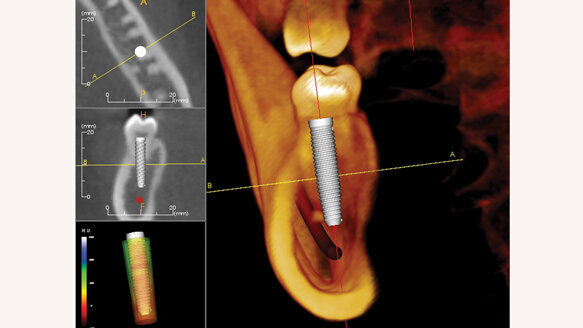

Obviously, with traditional two-dimensional radiographs, I could visualize the general location of these entities and approximate the height of the alveolus, but a 3-D scan provided more information about the morphology of that ridge — its height and width to within a hundredth of a millimeter as well as its angulation and variation of its form. Currently, I feel that the scope of data garnered from the CBCT is imperative to place implants safely and correctly for the best restorative options, and this technology has indeed, altered my approach to dentistry. I continue to learn from each case that I perform by acquiring low-radiation limited postoperative scans, which help me become a better surgeon.

The clear, virtual, revolving model of the dentition captured on the CBCT scan can be rotated, zoomed in on from any angle and viewed in 360 degrees to assist in the determination of the implant site as well as for the fixture’s proper inclination, length and diameter. As an added benefit, there are numerous CBCT-compatible, implant-positioning software programs available, such as SimPlant, NobelGuide, EasyGuide and Anatomage’s InVivo5.